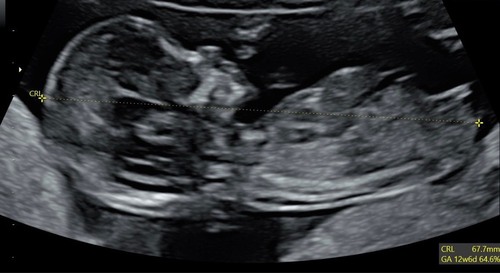

Hoi, hoi! Ik ben wel nieuwsgierig of het uiteindelijk klopt ja of nee! Heb het tijd geleden ook gedaan bij early glimpse EN nub techs… met 90 en 95 procent zeker met 12+2…

Vind het speculeren heel leuk vooral!